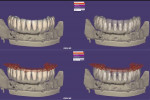

In the laboratory, the titanium framework was digitally scanned with the extraoral scanner (Activity 880), and the STL file was overlapped with the previous STL file of the conversion prosthesis, which had been saved into the CAD software (Exocad DentalCAD).10,12 With the aid of the CAD software, single crowns were digitally designed, and they were milled on a CAM milling unit (Tizian Cut Eco plus, Schuetz Dental, schuetz-dental.de/en) from prefabricated lithium-disilicate blocks (Figure 9 and Figure 10).10,12,16 Gingiva-colored composite resin (GRADIA®, GC America, gcamerica.com) was used. The lithium-disilicate single crowns were etched for 20 seconds with 4.9% hydrofluoric acid, rinsed with water for 1 minute, and air-dried with oil-free air.10,16 Then, silane coupling agent (Clearfil™ Ceramic Primer, Kuraray, kuraray.com) was applied on the crowns before adhesive cementation was performed with self-adhesive resin cement (Clearfil™ SA Cement, Kuraray).